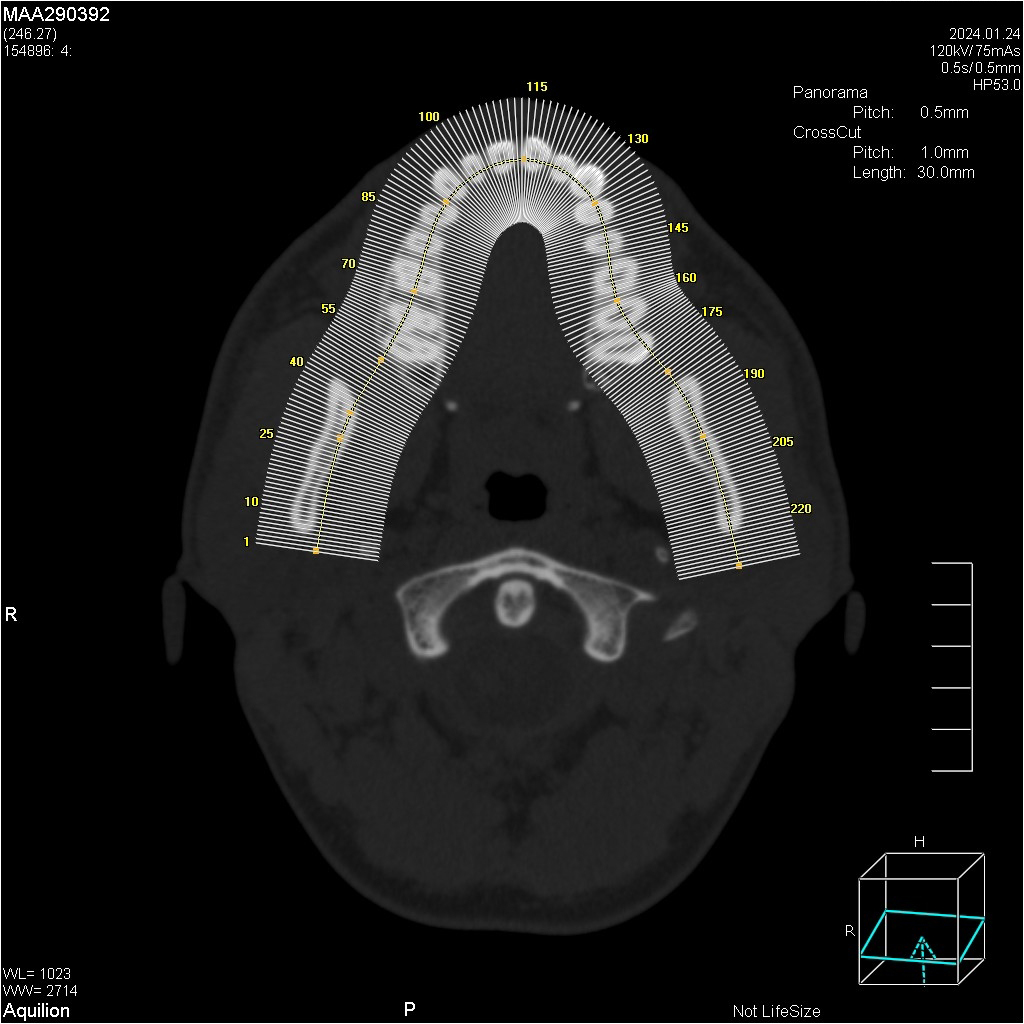

Мультиспиральный томограф выполняет послойное сканирование области верхней и нижней челюстей с помощью рентгеновских лучей, а затем, используя компьютерную обработку данных, создает 3D-модели исследуемой зоны. Современные модели томографов проводят круговое сканирование по спирали, делая срезовые снимки на расстоянии 0,5 мм друг от друга. Затем на основе этих данных реконструируются детальные изображения челюстно-лицевой области в трехмерном формате.

Как проводится обследование

Чтобы сделать КТ зубов, никакая предварительная подготовка не требуется. Непосредственно перед процедурой нужно снять очки, украшения, съемные протезы и вставные челюсти, слуховой аппарат, заколки для волос. Любые металлические предметы могут стать причиной появления артефактов (ложных затемнений) на снимках КТ зубов. Это может снизить информативность обследования.

Для защиты жизненно важных органов от воздействия рентгеновского излучения на шею и грудь надевают свинцовый фартук. Пациент располагается в положении лежа, предварительно сомкнув челюсти в положении привычной окклюзии (привычно закрытого рта).

Процедура не сопровождается неприятными ощущениями и абсолютно безболезненна. Необходимо только сохранять неподвижность, не глотать.

Исследование занимает всего пару минут. Данные, полученные при сканировании, проходят цифровую обработку и выводятся на монитор компьютера в виде 3D-изображений. Врач-рентгенолог внимательно анализирует данные и выдает заключение.